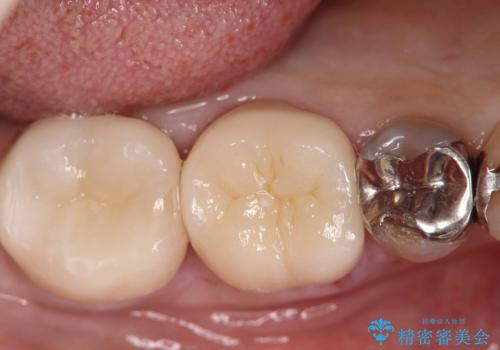

【セラミックインレー】咬合面のカリエス

- メンテナンス時に見つかった虫歯です。二次カリエスのリスクを下げる為に虫歯を除去後セラミックインレーで治療を行いました。

咬合面の溝が深く虫歯のリスクが大きい患者様です。

他の歯も咬合面に同じように虫歯ができて大きくなってしまった経験があることから今回は大きくそして深く進行する前に虫歯を除去しセラミックインレーで治療を行いました。